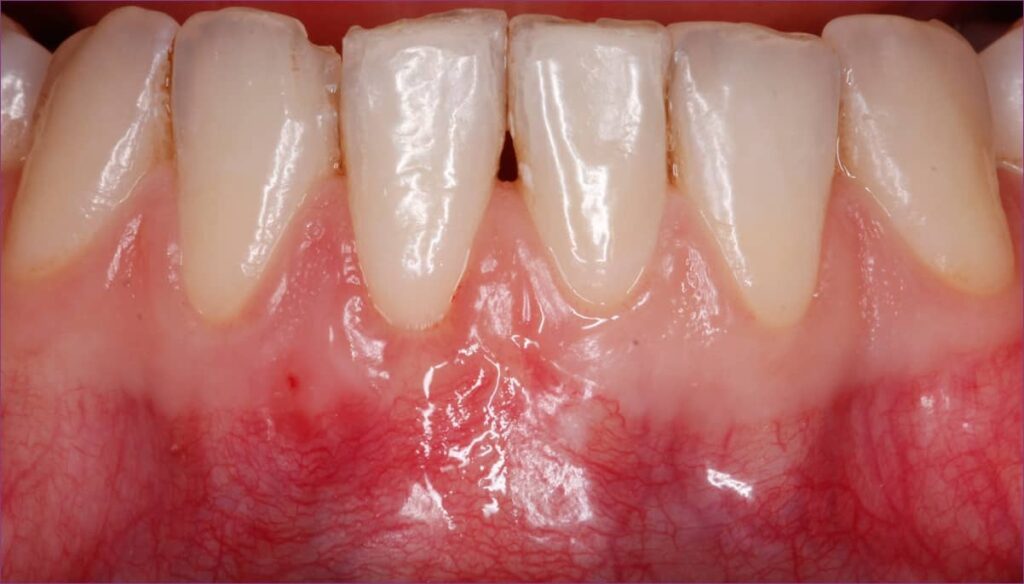

Fiatal hölgy azzal a panasszal fordult Dr. Orbán Kristóf parodontológushoz, hogy a jobb alsó első metszőfogáról az íny visszahúzódott (ez az ínyrecesszió), foga érzékennyé vált.

ínyrecesszió kezelés előtti állapot